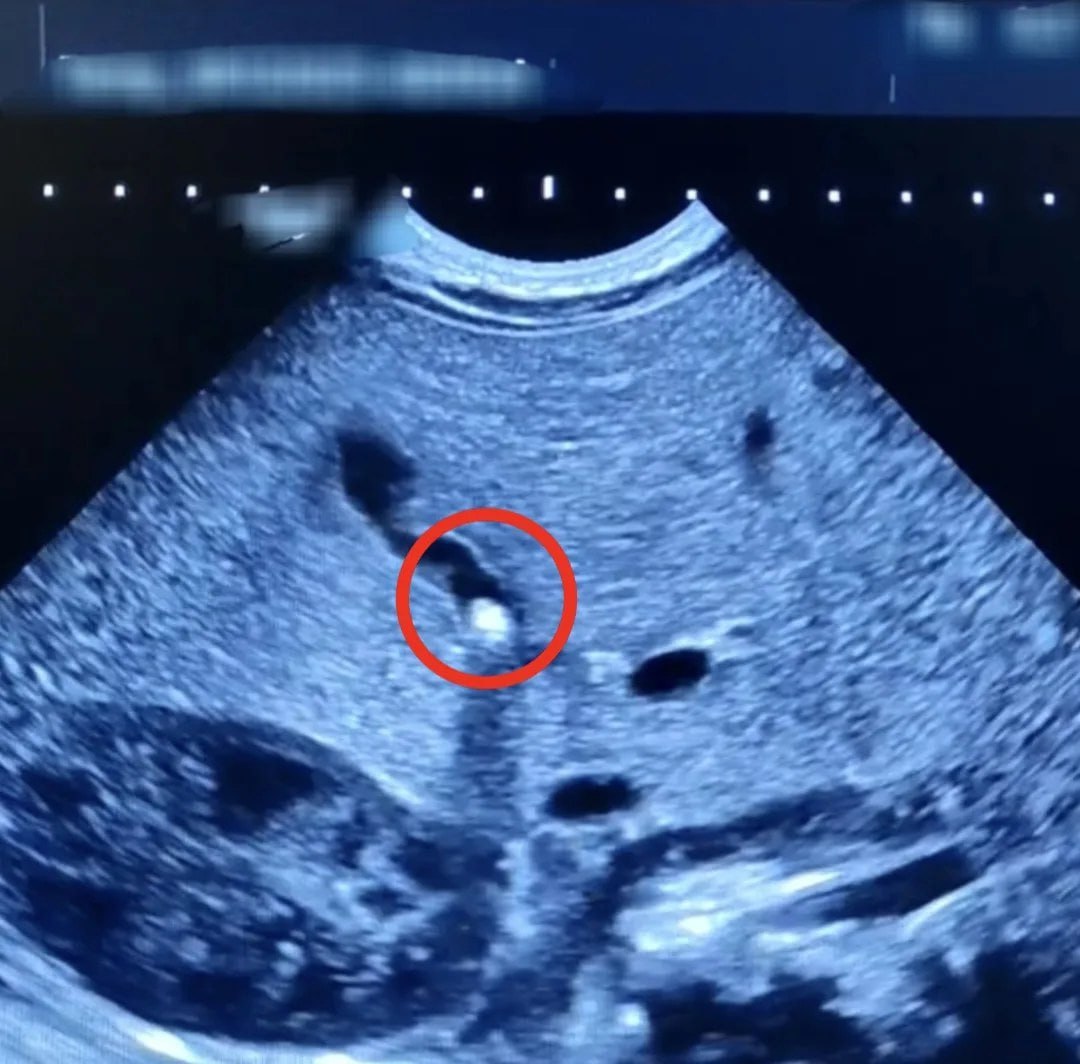

При обследовании выяснилось, что желчный проток частично закрыт камнем небольших размеров. Медикам удалось не только нормализовать отток желчи из желчного пузыря, но и добиться прибавки в весе, которой не было в первый месяц жизни ребенка. Сейчас малыша выписали.